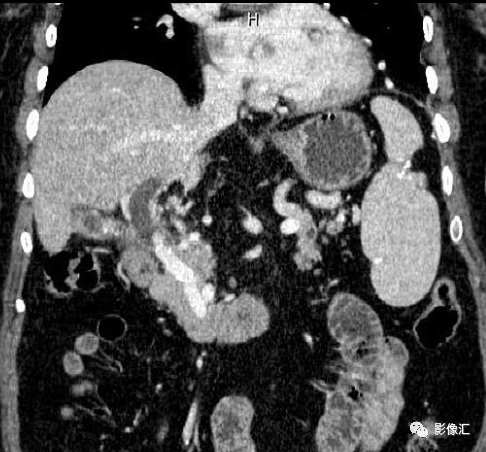

70岁女性,腹痛、黄疸就诊。

影像所见:胆囊已切除,肝内胆管和肝外胆管扩张,胆总管远端结石。门静脉区域可见多发迂曲血管丛结构,与门静脉海绵状变一致,迂曲的血管丛对胆总管局部造成压迫。脾脏增大,高度测量为 158 毫米。

病例结果:门静脉海绵样变性

(一)门静脉海绵样变直接征象动态增强CT扫描门静脉期,于肝门区门静脉主干周围及肝内门静脉左、右支周围见大量迂曲、扩张的静脉血管丛为诊断门静脉海绵样变的最直接征象(图1A)。正常情况下,门静脉周围仅见肝固有动脉伴行,极少数可见胃右动脉或胆囊动脉显影或存在解剖变异,故通常以门静脉周围出现多于3个血管断面作为侧支循环开放标准。门静脉海绵样变患者肝门区正常门静脉结构消失(图1),或见门静脉管腔内充盈缺损影(癌栓或血栓)(图2,3),门静脉周围开放的侧支静脉迂曲、扩张,呈结节或团块状表现,直径不一,而且在静脉期明显强化;肝裂内,门静脉左、右分支明显变细或显示不清,周围亦见多发的蜂窝状侧支血管,向肝门区延续并逐渐增粗,呈海绵状改变,为门静脉海绵样变典型表现。

(三)胆胰管继发性病变由于胆管周围静脉迂曲、扩张,门静脉海绵样变患者胆总管不规则受压、变窄常见,可呈波浪状或结节状外观。ERCP造影表现为胆管无规律、多发小结节状的外压性缺损,称为“假性胆管癌征”(pseudocholangiocarcinoma sign)。多层螺旋CT动态增强扫描门静脉期薄层图像可见强化的胆囊静脉和胆管周围静脉丛紧贴胆总管和胆囊壁外缘,压迫管壁造成波浪状或局限性凹陷,局部管腔狭窄,其上方胆总管、肝门区胆管及肝内胆管轻度扩张(图5)。伴有继发性胆管周围纤维化改变时,还可见胆管壁不规则增厚,范围较广,可与胆管癌鉴别。胰十二指肠后上静脉曲张还可压迫胰管造成胰管扩张(图7),发生率约占门静脉海绵样变患者的85%。